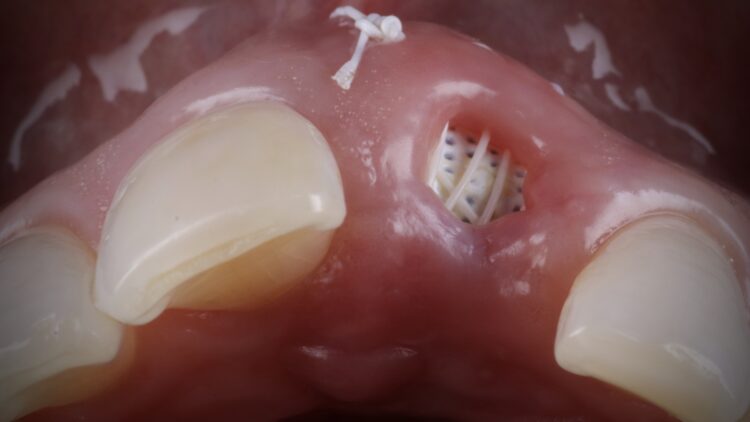

It was thus decided to carry out a ridge preservation graft to retain the existing alveolar ridge width and to use an open healing concept to encourage new soft tissue growth, increase keratinised tissue and avoid distortion of the mucogingival junction. This was carried out using the combination of MinerOss® Blend Allograft and a dense PTFE membrane.

Once the orthodontic treatment was completed, the site was re-evaluated, and it was clear to see that the gingival zenith had significantly improved. The patient was advised that without re-contouring the mesial aspect of the contralateral central incisor there would be a midline black triangle. She rejected the option of composite addition to alter the triangular shape of the UR1 and thus we proceeded to complete the treatment without this. The implant was placed with simultaneous buccal GBR & connective tissue graft following a transmucosal approach. Following a healing period of 4 months, the restorative treatment was initiated with a temporary crown to develop the emergence profile. Once the gingival zeniths had been matched, the patient was delivered a permanent screw retained crown.

This case demonstrates the power of ridge preservation whereby significant hard tissue grafting was avoided entirely in a patient with an extremely thin maxillary alveolus. The improvement in soft tissue contours is evident to be seen even with a healing period of 18 months post extraction with excellent keratinised tissue volume and no distortion in the mucogingival junction.